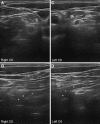

Results: Fifteen adult VEGBS patients were identified with a mean age of 57.8 years. At first NCS, VEGBS sub-typing was only possible in 3 (20%) cases that showed an axonal pattern, the remaining patterns being mixed (combining axonal and demyelinating features) in 6 (40%), equivocal in 5 (33.3%), and normal in 1 (6.7%). Upon serial NCS, 7 (46.7%) cases were categorized as acute demyelinating polyneuropathy, 7 (46.7%) as axonal GBS, and 1 (6.6%) as unclassified syndrome. Antiganglioside reactivity was detected in 5 out of the 7 axonal cases. Nerve US showed that lesions mainly involved the ventral rami of scanned cervical nerves.

Conclusions: Serial electrophysiological evaluation is necessary for accurate VEGBS subtype classification. Ultrasonography helps delineate the topography of nerve changes.